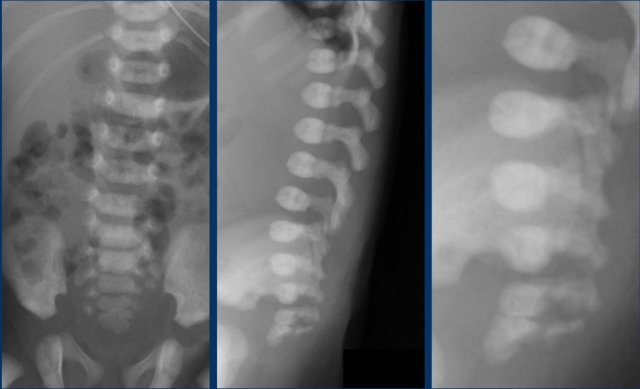

The best way to determine the position of the conus medullaris is by identifying the lumbosacral junction at the lordotic angle between the lumbar and sacral vertebrae (arrow).

It can be helpful to flex and extend the pelvis to see the point of motion of the sacrum.

In this newborn the lumbosacral junction is less clearly seen because there is no acute angle.

The numbers that we've put in, might be wrong.

If one is uncertain, make a panoramic or dual image of the lumbosacral vertebral column and compare the vertebral count from below upwards with a lateral plain film.